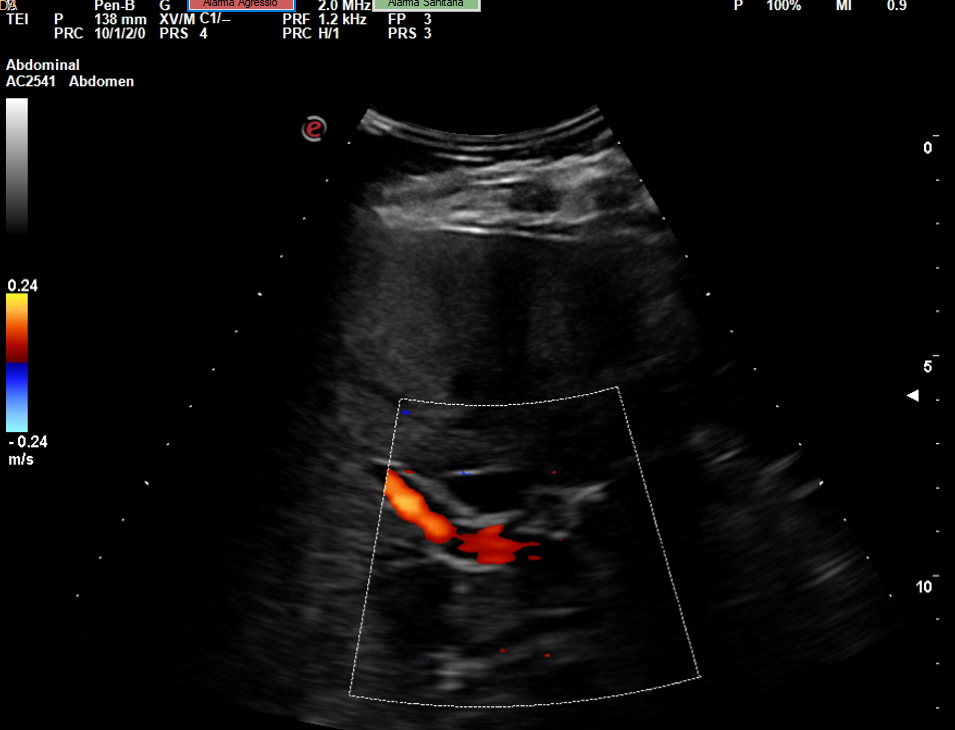

Se realiza la ecografía abdominal en el ambulatorio, donde se objetiva colelitiasis con el colédoco en el límite superior de la normalidad (4,4 mm), también presenta esteatosis hepática grado I. El resto de la ecografía no presenta hallazgos de interés.

Colelitiasis con colédoco en el límite de la normalidad.